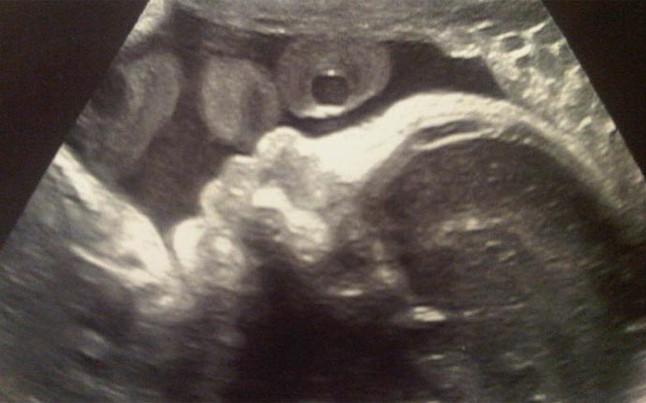

Εντάξει, δεν πρόκειται για φωτογραφία, αλλά δεν παύει να αποτελεί την πρώτη… εικόνα του γιου που περιμένουν ο Ζεράρ Πικέ με τη Σακίρα.

Ο προσεχώς χαζομπαμπάς αμυντικός της Μπαρτσελόνα έσπευσε να δημοσιεύσει στη σελίδα του στο Twitter μία εικόνα από το υπερηχογράφημα που έκανε η Κολομβιανή ποπ σταρ.

«Η πρώτη του φωτογραφία», έγραψε ο Καταλανός άσος.